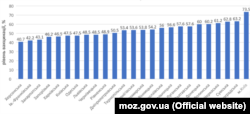

За офіційними даними, лише 53% дітей отримали вакцину проти поліомієліту. Це вкрай мало, зауважив головний санітарний лікар України Ігор Кузін, адже для формування в державі колективного імунітету кількість вакцинованих має бути 95%.

Ситуація в регіонах

Нині кожна з областей має усі шанси стати місцем поширення вірусу, кажуть медики, проте найбільш загрозлива ситуація склалась у:

- Херсонській

- Харківській

- Закарпатській

- Івано-Франківській областях.

Вищий рівень вакцинованих у

- Києві

- Кіровоградській

- Сумській

- Черкаській

- Волинській областях